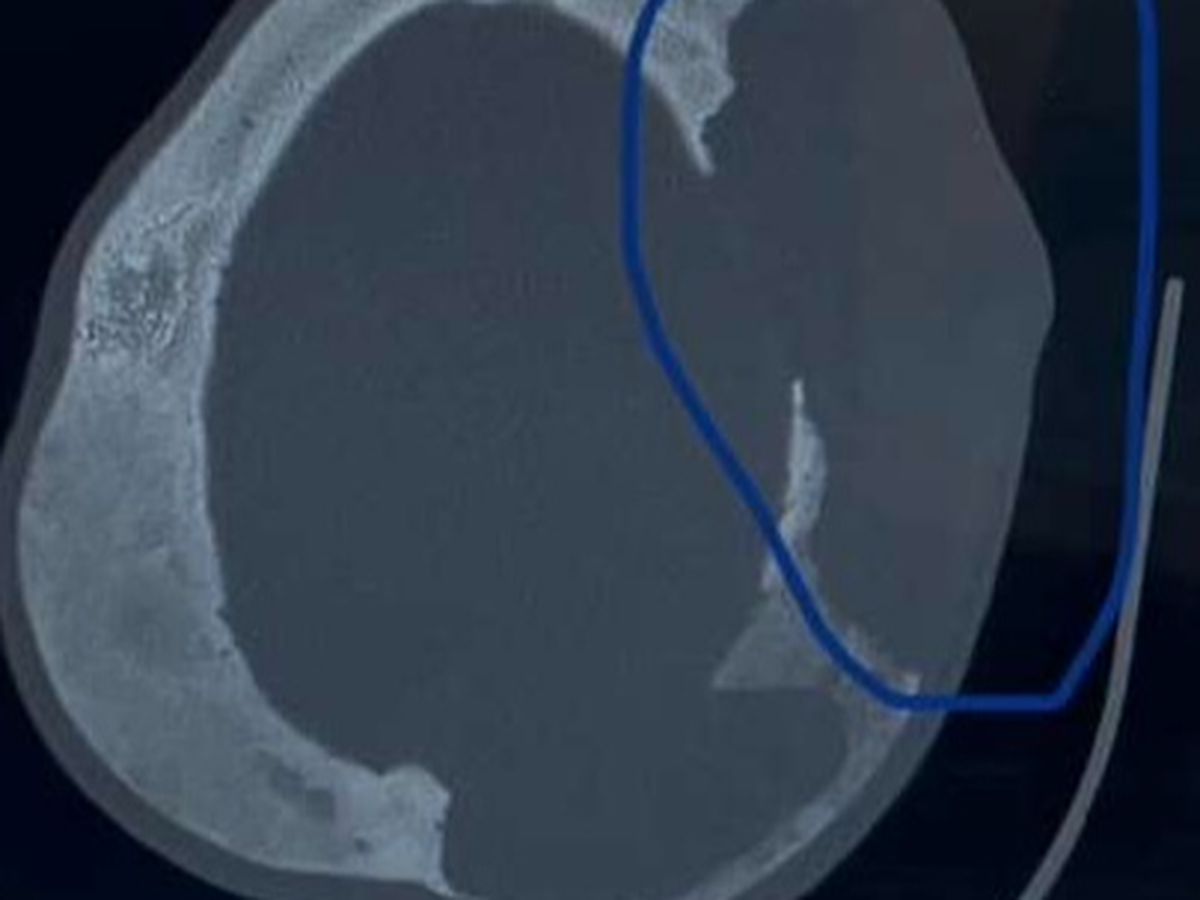

On October 24th, Wil noticed a sore spot on his skull. Scans revealed a bone cyst, and subsequent scans showed three more growing rapidly. The largest cyst broke through his skull, creating a hole and a blood-filled lump. Thankfully, the cysts are not malignant. After consulting craniofacial and neurological specialists at WCH, it was decided to avoid radiation therapy or skull surgery. Instead, Wil began a series of injections aimed at "switching off" the osteoclasts in his bones to allow bone rebuilding. After 4 injections in December, Wil will need monthly injections for six months. The initial treatment is showing promise, but the journey is far from easy.